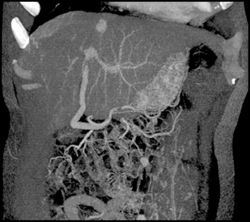

Islet Cell Tumor With Liver Metastases